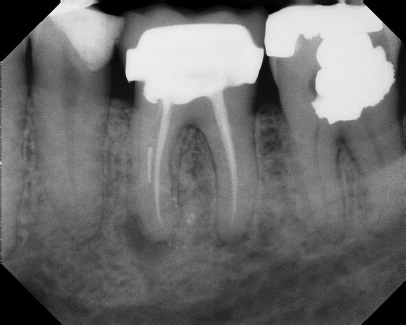

COMPLICATED ANATOMY LARGE LESIONS CALCIFIED CANALS PERFORATION / RESORPTION SEPARATED INSTRUMENTS SURGICAL CASES RETREATMENT / pOST REMOVAL OPEN APICES ACCESS THRU CROWNS Root Canal Case Portfolio

Pre-op Post-op 1 Post-op 2